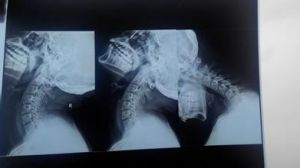

頸椎失穩症又稱頸椎不穩症。頸椎失穩是指頸椎在生理載荷下,解剖上超出其生理限度的位移範圍,且出現相應的臨床症狀引起的一種綜合徵。隨著現代生活的日益緊張,其發病率呈上升趨勢,並成為頸肩痛、頭暈痛、胸悶,甚至雙上肢麻脹痛更為常見的原因。

頸椎失穩人體頸椎的穩定性系由兩大部分來維持:一是內原性穩定,包括椎體、椎弓及其突起、椎間盤和相連的韌帶結構,為靜力性平衡;二是外原性穩定,主要為頸部肌肉的調節與控制,它是脊柱運動的原始動力,為動力性平衡。上述任何一個環節遭受破壞,均可能引起或誘發頸椎正常結構及平衡功能的喪失,從而導致頸椎不穩。

頸椎的穩定性在力學範圍內用剛度來衡量;當頸椎因各種原因導致其結構功能減退時,活動節段的剛度就會降低,於是在生理載荷下便會出現過度活動和(或)異常活動,這就是頸椎失穩;若由此引起一系列相應的臨床表現,並且存在潛在的進行性畸形和神經損害的危害,就稱為頸椎失穩症。在諸多病因中,退行性變最為常見。椎間盤是人體組織中發生退行性變最早的部位。主要表現為蛋白多糖和水分含量的減少以及非膠原蛋白成分的增加。